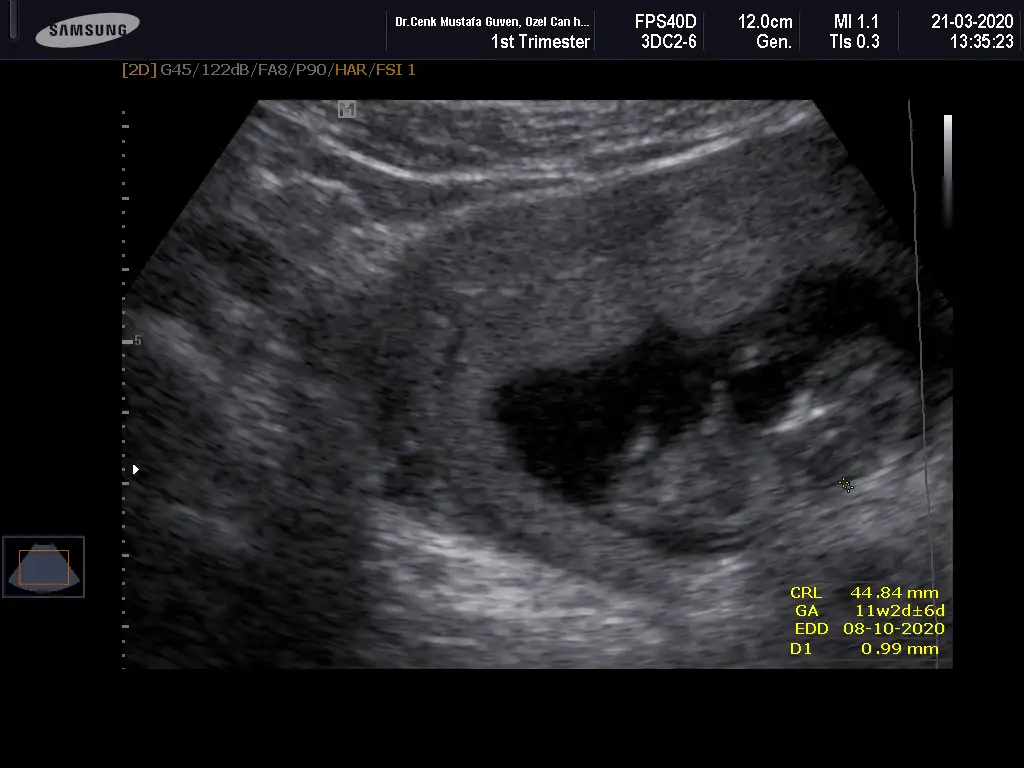

Banada bakarmısınız şimdi ikili testten çıktım doktor erken dedi soylemedi çok merak ediyorum 12 haftalik

Merhabalar, ctesi ikili test icin gittim 11+6 idim. Suana kadar hep haftayla uyumlu giderdi sat. Ama bu sefer 12+6 cıktım. Yine de cinsiyet yorumlar mısınız? Gec mi kaldım? Bir de doktor tahminini söyledi ama emin değil. Kafanız karışmasın diye en son söyleyeceğim.